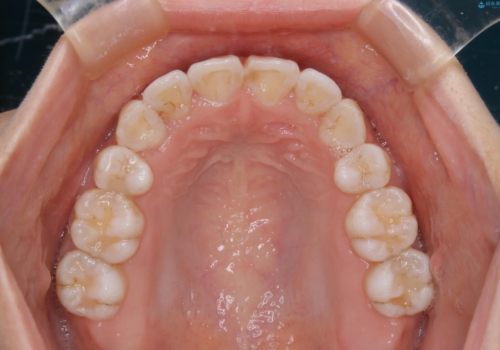

インビザライン単独での抜歯矯正治療

- 当院にてインビザライン治療を行っていた同僚の方からのご紹介でいらした方です。楽器を演奏されるとの事で、インビザラインによる矯正治療をご希望されました。治療の途中で一時的にワイヤー矯正に切り替える可能性もあることもご了承頂いた上で治療を行いました。

1日20時間以上、正しくインビザラインを使用して頂いたおかげで、ワイヤーに切り替えることなく矯正治療を終了することが出来ました。抜歯症例でしたが比較的短期間で見た目が劇的に改善し、大変喜んでいただけました。